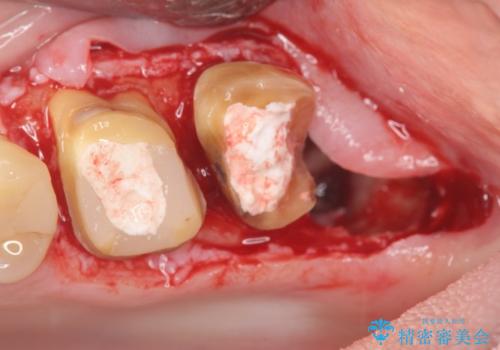

銀歯を除去したところ、虫歯が大きく再発しこのままではかぶせ直しができないような状況でした。

・深い虫歯 →歯周外科を行うことで歯ぐきの腫れを改善